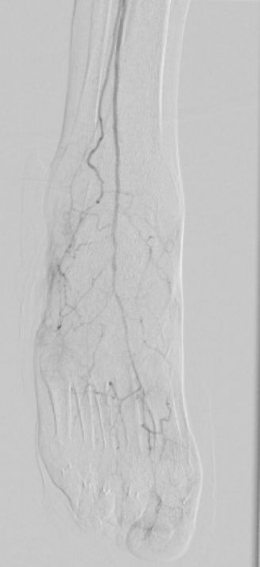

7. 术后造影血流恢复

本例患者股浅动脉重度闭塞,股浅远端重度钙化病变近收肌管,利用Shockwave冲击波球囊获得满意的管腔准备后联合使用DES,为保障远期通畅植入支架,支架膨胀形态理想。

我国患者股浅动脉又多以长段闭塞病变为主,为保障远期通畅率,支架的植入往往不可避免,此时如何优化支架膨胀则至关重要。利用“聚焦式”的冲击波能量作用于重度钙化环最薄弱处,在低压下安全打开钙化斑块,尤其是限制血管床弹性的环形钙化,可有效增加管腔顺应性,减少弹性回缩。